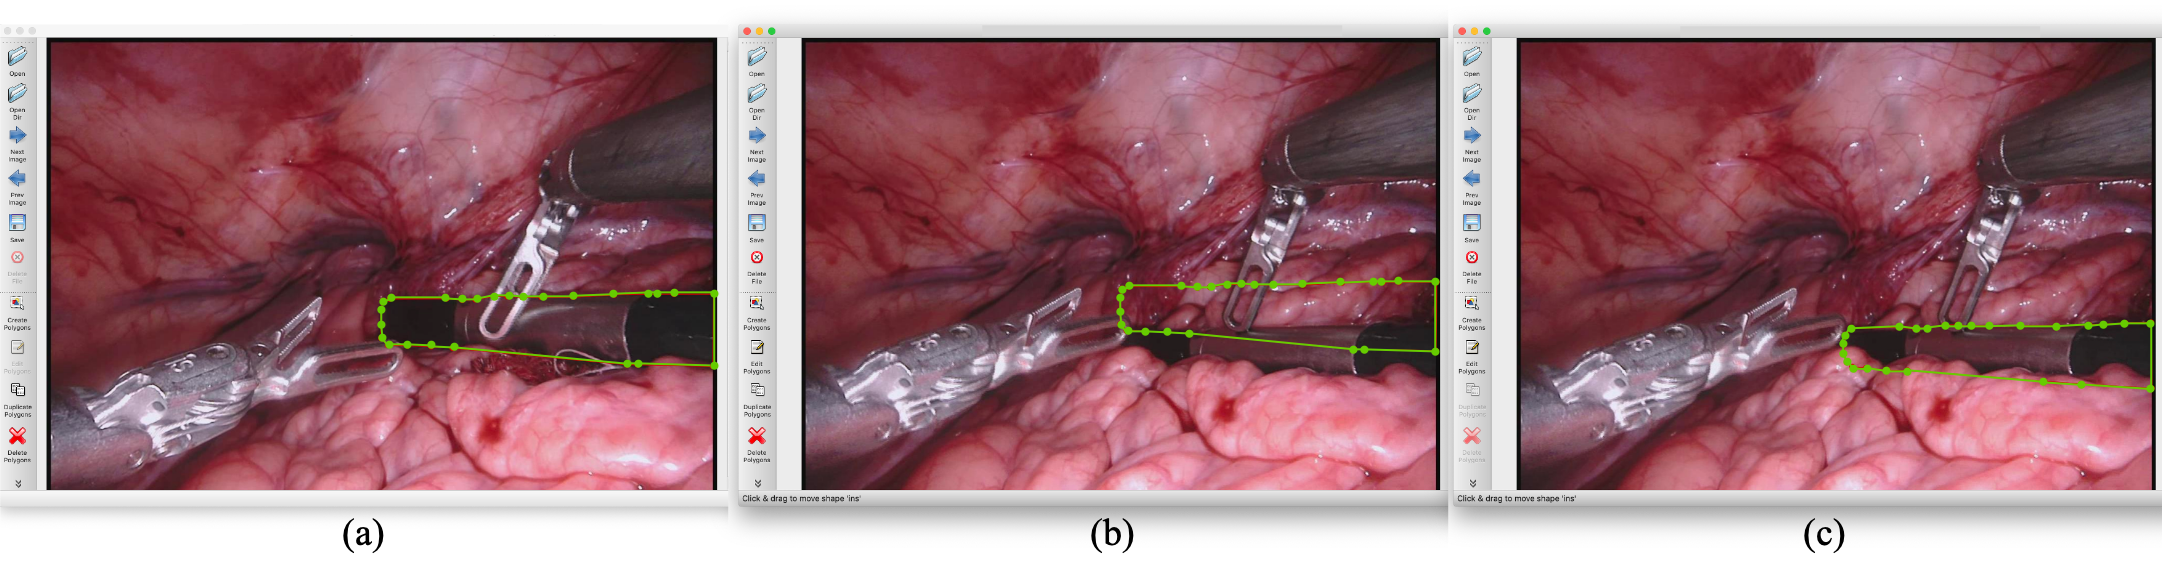

Consider a practical example of our annotation methodology as illustrated in Fig.2(a), the middle instrument is annotated with a polygon that includes several key points and line segments. In this interface, annotations can be refined by adjusting the positions of key points (illustrated as green points). After completing the annotation for one frame, it can be carried over to the next frame, as depicted in Fig. 2(b). Given that the movement of surgical instruments between consecutive frames is typically minimal, the annotation for the current frame can often be achieved by simply repositioning the key points from the previous frame to align with the instrument’s shape. This process completes the annotation for the middle instrument in the current frame, with the final result displayed in Fig. 2(c). By employing this annotation strategy, we attempt to reconstruct the original form of the instruments as accurately as possible, even for occluded parts. Our guiding principle is to ensure that the prediction of the occluded sections adheres closely to the instrument’s actual shape and follows its natural motion trajectory.

Figure 2: Illustration of annotation process. (a) displays a polygon annotation formed by various key points and line segments. Once the labeling of this frame is complete, the annotation can be carried forward to the next frame for further labeling, as depicted in (b). By adjusting the positions of the key points within the polygon, the final annotation of the instrument in (b) is presented in (c).